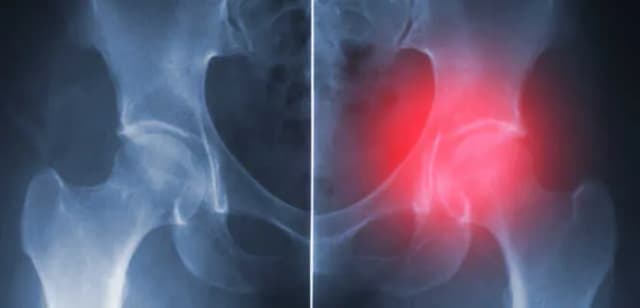

Tag które endoprotezy stawu biodrowego są na liście refundacyjnej nfz